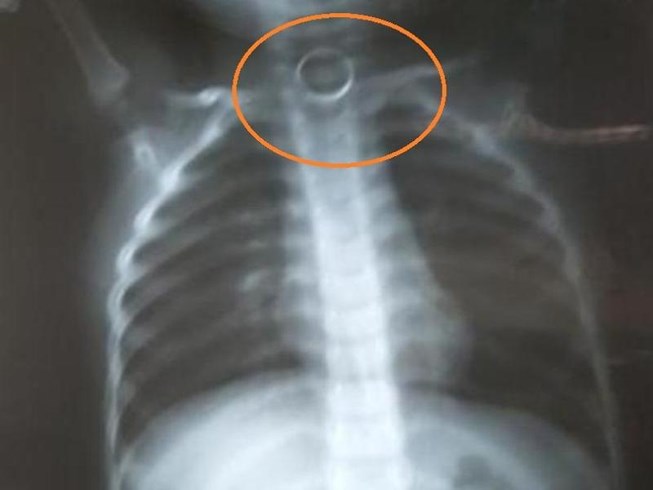

Qua chụp X quang, bác sĩ phát hiện vòng kim loại đường kính khoảng 2cm nằm ở thực quản ngang đốt sống cổ số 6-7 của bé. Để an toàn cho bệnh nhân, đồng thời do BV chưa đủ các kỹ thuật hỗ trợ như ống nội soi cho trẻ nhỏ, bác sĩ trực đề nghị chuyển bệnh nhân đi Hà Nội.